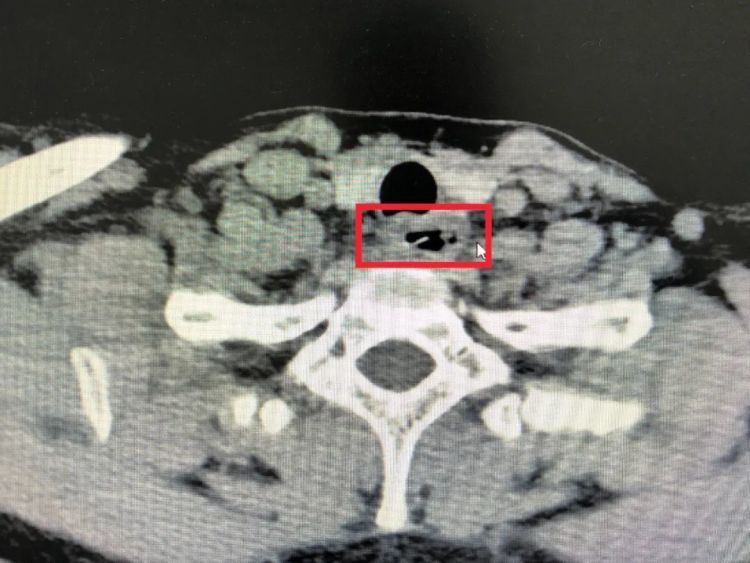

为准确判断异物的大小和位置,医生先为陈女士安排了喉镜检查,但由于鱼刺位置较深,喉镜无法照到。随后,医生又安排了食道CT和胃镜检查,最终发现距门齿18cm处,一根较大根的鱼骨横嵌在食管壁上。

医生表示,若不及时处理,这根鱼刺极有可能刺穿食道和心脏主动脉,严重危及生命。幸运的是,在医生的及时处理下,鱼刺很快被成功取出。